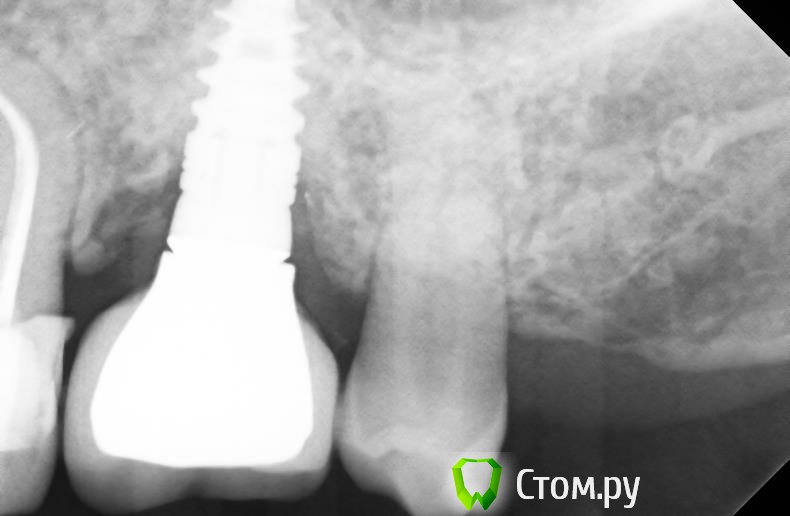

bullbull Опубликовано 20 марта, 2014 Поделиться Опубликовано 20 марта, 2014 Предыстория: мужчина 32 г. Установлен имплант SPI 4,2, 10 в позиции 26. ФДМ через 5-6 месяцев. После фиксации коронки жалобы на постоянные ноющие боли в области имланта, застревание пищи. Мною проведен глубокий кюретаж, назначено лечение. Улучшение на несколько недель. Повторное обращение с теми же жалобами. Локально: некоторая гиперемия десны с вестибулярной стороны, глубина кармана до 3 мм, отделяемого нет. С небной стороны всё в норме.P.S. Нависающий край 25 сточен. У меня появился только после протезирования.Мои мысли: снять коронку, глубокий кюретаж с графтом, возможно, мягкотканная пластика после купирования воспаления, заглушка. А потом всё по новой, через пару месяцев.В общем, нужен совет. Заранее, спасибо. Ссылка на комментарий

АнтонТЛТ Опубликовано 20 марта, 2014 Поделиться Опубликовано 20 марта, 2014 Ремоделировка кости на том уровне на котором должна быть, но из-за слишком глубокой установки имплантата появился глубокий карман. Графт не поможет. Я бы выкрутил и переставил на нужную глубину. 1 Ссылка на комментарий

r3yand Опубликовано 20 марта, 2014 Поделиться Опубликовано 20 марта, 2014 А что за дизайн абатмента?Он сам создает нависающий край, там и происходит скопление пищи имхо. Какой-то обратный платформ-свитч получился... Ссылка на комментарий

kriokov Опубликовано 20 марта, 2014 Поделиться Опубликовано 20 марта, 2014 А что за дизайн абатмента?Он сам создает нависающий край, там и происходит скопление пищи имхо. Какой-то обратный платформ-свитч получился...тоже не торопился бы имплантат удалятьчто настораживает- видимые дефекты в посадке коронки на абатменте- какойто "мутняк" по переферии от абатмента, может цемента остатки?Снял бы с ортопедом конструкцию, ревизию этой зоны сделал бы, если цемент и грануляции до платформы, то удалил бы их, и фдм на месяц. 3 Ссылка на комментарий

carloss Опубликовано 20 марта, 2014 Поделиться Опубликовано 20 марта, 2014 а что тут думать - недосела коронка.. лечение - только терапия с ортопедией 2 Ссылка на комментарий

j-kost9 Опубликовано 20 марта, 2014 Поделиться Опубликовано 20 марта, 2014 Мои мысли,что коронка не села,+цемент,глубокая установка сыграло сыграло свою роль,т.к вы запрограммировали глубокую биологическую ширину,тем самым создались условия для инфекции.Если бы это был ан..лоз например думаю такой ремоделировки не было бы,опять же если это не цемент. Ссылка на комментарий